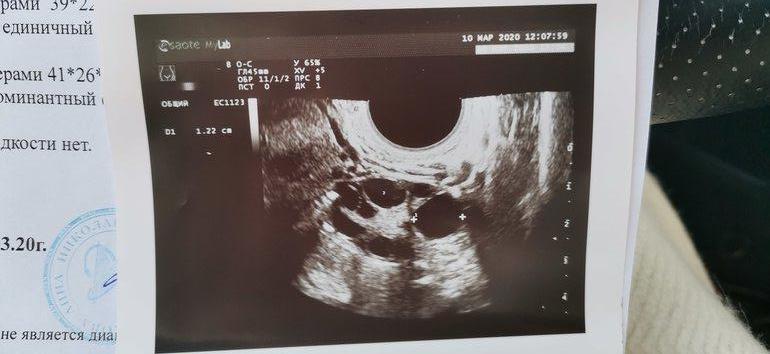

СтимуляцияДевочки! Стимуляция у меня 2-5 ДЦ 100МГ КЛОСТА, сегодня 9ДЦ, почуяла попой что срочно надо сходить на УЗИ И ВОТ ЧТО!

Что делать? ( это первая моя овуляции за все время, первая стимуляция и вот они доминанты!!! Но как быть с эндометрием помогите((